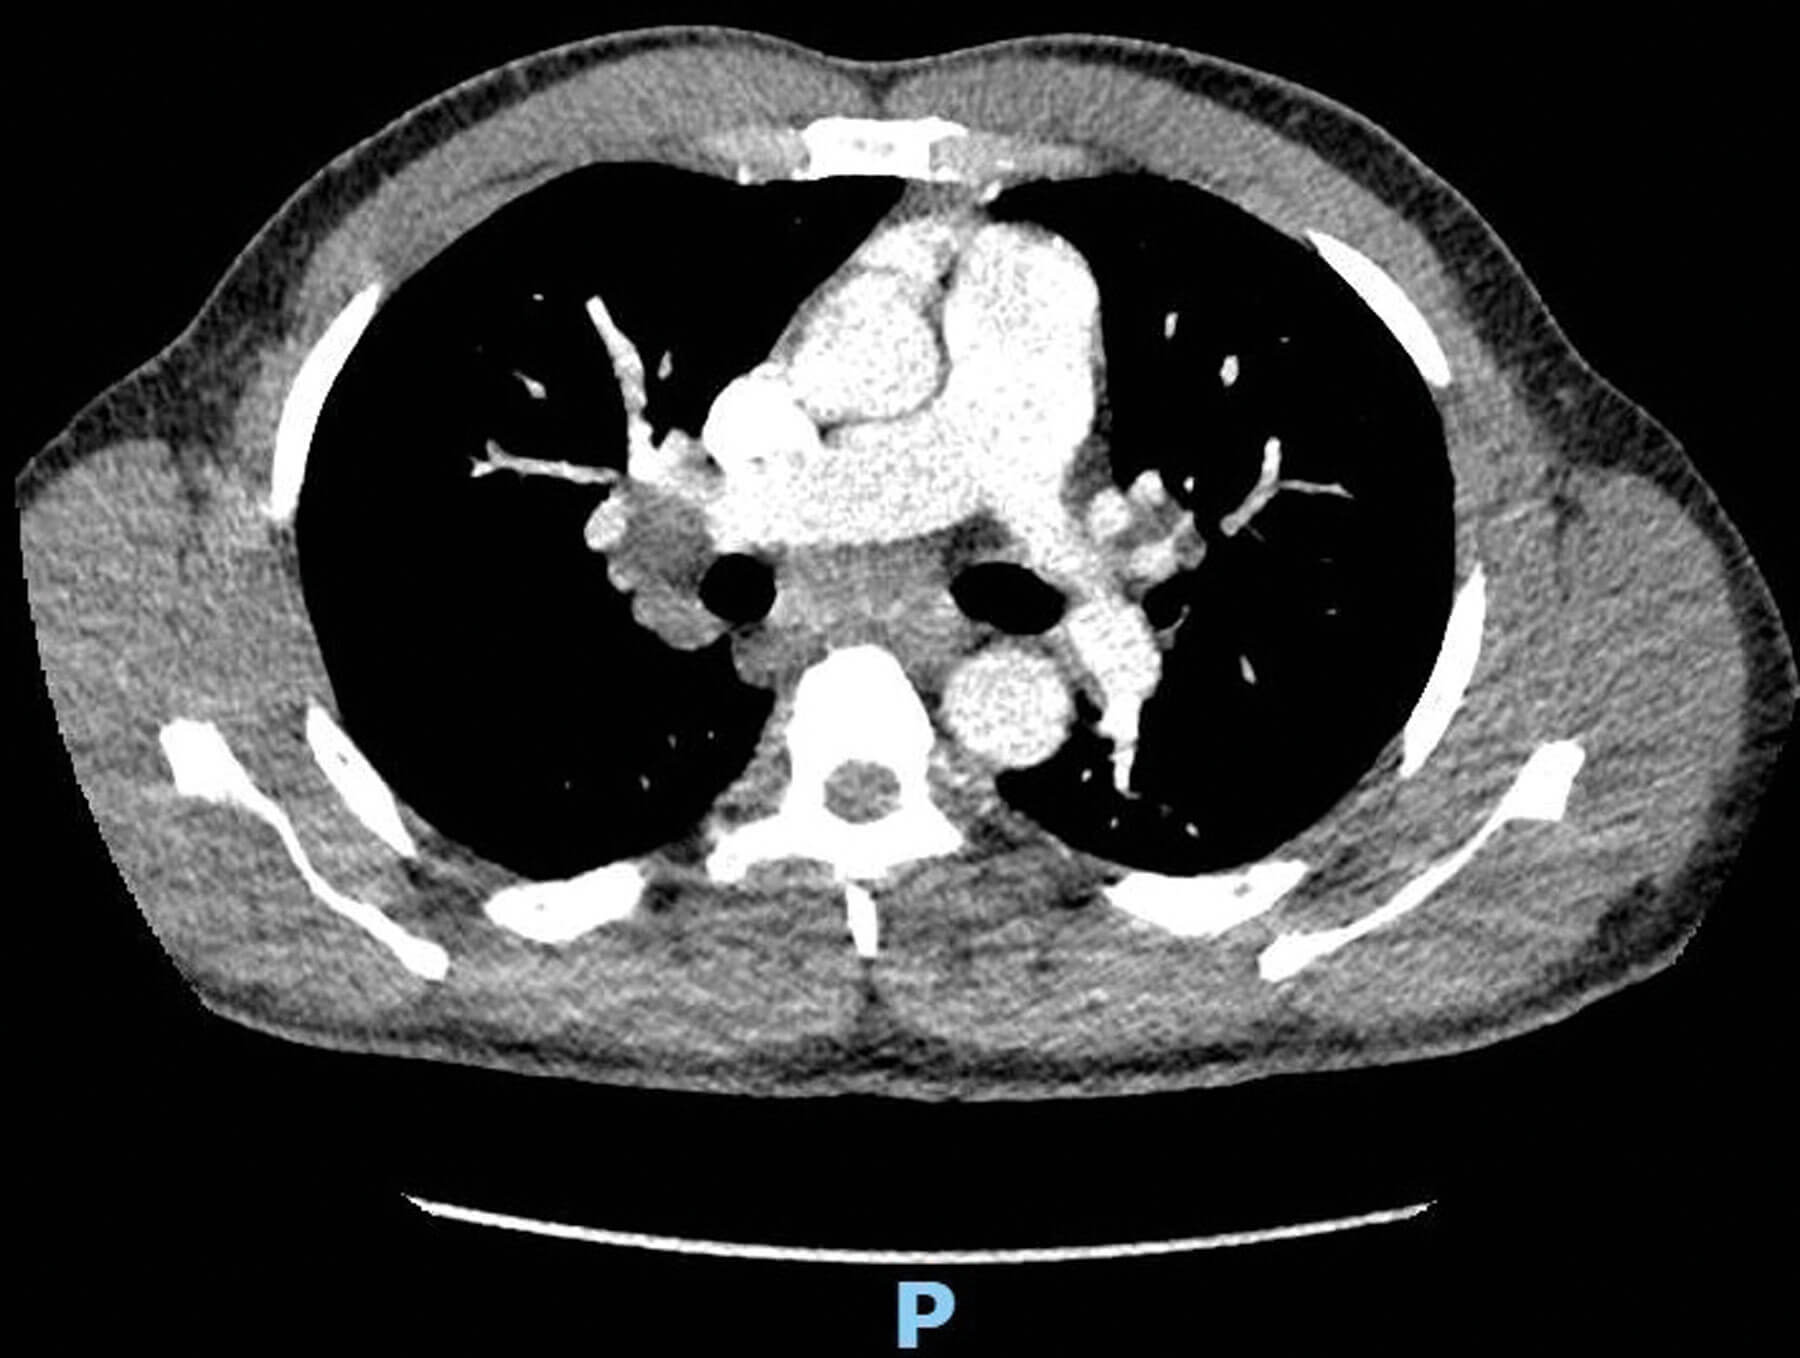

The patient’s uveitis responded well to topical treatment and his visual acuity returned to 6/5 bilaterally. He was referred to the respiratory team and a CT Thorax confirmed mediastinal and bilateral hilar lymphadenopathy (Figure 2).

Figure 2: CT Thorax showing bilateral hilar lymphadenopathy.